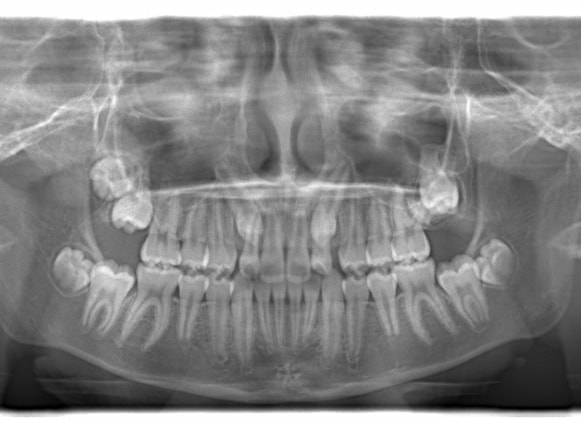

FX(フェイシャルアキシス)は85度なので東洋人の平均値に近く、下顎が前方に過剰成長するリスクは強くはありません。

しかしやはり上顎は劣成長で、下顎が優位な状態ではあります。

上下顎のギャップはありますが、顔面自体の幅径は良好な値を示していますので、スペース不足は拡大することによって解決できポテンシャルはあると考えられます。

左右の非対称もさほど強くありません。

骨年齢は実年齢よりも低めなので、今後下顎の旺盛な成長が見込まれます。

検査時のレントゲン分析では、上下顎の関係は、上顎の劣成長があり下顎前突傾向という値がでておりましたが、前歯ジャンプ後はフェイスマスクの効果もあり、上下顎の関係は正常化しています。

上顎が若干優位になっていますので、今後の下顎の成長のための貯金になっているくらいです。